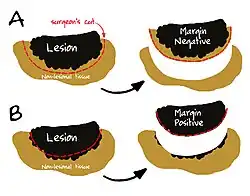

A resection margin or surgical margin is the edge or "margin" of apparently non-tumorous tissue around a tumor that has been surgically removed, called "resected", in surgical oncology. The resection is an attempt to remove a cancer tumor so that no portion of the malignant growth extends past the edges or margin of the removed tumor and surrounding tissue. These are retained after the surgery and examined microscopically by a pathologist to see if the margin is indeed free from tumor cells (called "negative"). If cancerous cells are found at the edges (called "positive") the operation is much less likely to achieve the desired results.[1]: sections 1-2

- Negative margin: No tumour at the margin.

- Microscopic positive margin: Tumour identified microscopically at the margin.

- Macroscopic positive margin: Tumour identified grossly at the margin.

Surgical margin in a surgery report defines the visible margin or free edge of "normal" tissue seen by the surgeon with the naked eye. Surgical margin as read in a pathology report defines the histological measurement of normal or unaffected tissue surrounding the visible tumor under a microscope on a glass mounted histology section.[4][5] A "narrow" surgical margin implies that the tumor exists very close to the surgical margin, and a "wide" surgical margin implies the tumor exists far from the cut edge or the surgical margin. Narrow surgical margin using the bread loafing technique suggests that residual cancer might be left due to false negative error. A surgeon often will perform a second surgery if a narrow surgical margin is noted on a pathology report.